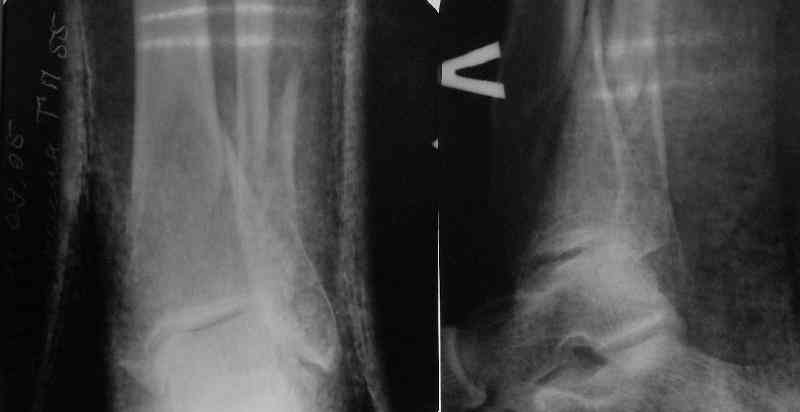

From the Xrays it seems as though the proximal fracture is relatively undisplaced. I thought that Poller screws were mostly used to prevent displacement of the fracture while the nail was being inserted. In this case I would think that you could hold the reduction temporarily either with a clamp, crossed K wires or a lag screw. Then insert the nail and place a proximal blocking screw only if you need to. Will the proximal locking screws fix the proximal fragment? Are you going to fix the fibula?

A typical case is attached, also an image with intra-op reduction obtained by a small wire distractor, in the moment of insertion a Poller wire in AP direction. Fixation by a SIGN nail. Despite the fibula was not fixed healing was obtained with the unchanged alignment.

Very interesting application, but is the final position in a little distal varus with some fibula

At least both the ankle mortise and tibial alignment look acceptable, don't they?

I am just trying to illustrate that prevention of 1)tibial valgus and 2)loss of reduction can be provided without fibular plating. Small changes of conventional nailing techniques allow to maintain reduction of the tibia reliably without adjunctive fibular stabilization.